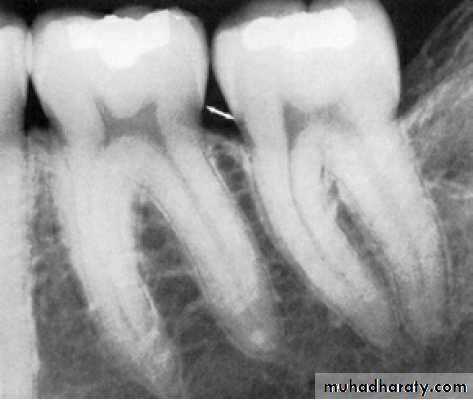

Furcation Involvement:

the pathologic resorption of interradicular bone within a furcation of a multirooted tooth due to periodontal disease. Classification:Ι, ΙΙ, ΙΙΙ, ΙV

• Special probe:

Nebers 2 , Za 3

Radiograph can detect 2 & 3

FI. Assessed all the entrances of possible periodontal lesion of multirooted teeth:

Buccal and /or lingual of mandibular molars.

Maxillary molar and premolars/ buccal /distopalatal/ mesiopalatal.

Due to furcation between MB and P:explored from palatal aspect.